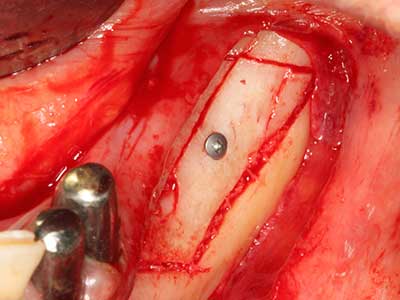

En la extracción de bloques óseos la piezocirugía también presenta ventajas adicionales: Además de la alta precisión en la osteotomía que ya se ha descrito antes, se ha comprobado que el uso de los delgados insertos de sierra resulta especialmente cuidadosas con el hueso. Frente a esto, sobre todo cuando se usan las fresas de Lindemann, cabe esperar pérdidas en la extracción significativamente más altas debido al mayor grosor de la parte frontal del cabezal (Lakshmiganthan, Gokulanathan et al. 2012). La separación basal que se necesita en particular en los injertos de bloque extraídos de forma retromolar se ve facilitada mediante sierras perpendiculares especialmente previstas a tal fin, lo que permite considerar que la cirugía piezoeléctrica es un procedimiento preciso y seguro para la obtención de bloques de hueso en el área retromolar (Happe 2007) (fig. 1-12).

Como ya se ha demostrado en el pasado, básicamente cualquier procedimiento de cirugía de hueso representa una posible indicación para la cirugía piezoeléctrica. Así, la preparación del segmento móvil en la osteogénesis de distracción (fig. 23-25) y en la osteotomía de sándwich puede realizarse con piezas especiales, sin poner en peligro el suministro sanguíneo de la parte crestal, que resulta esencial para el éxito de ambas técnicas (González-García, Diniz-Freitas et al. 2008).